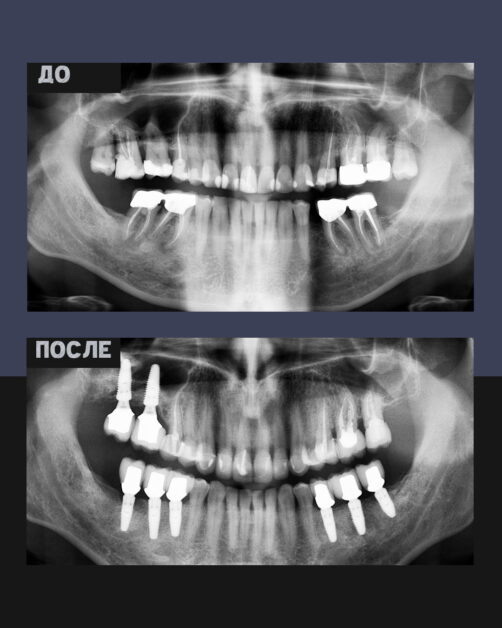

У пациента диагностировали множественное отсутствие зубов, выраженные нарушения прикуса и воспалительные заболевания пародонта. Данные проблемы вызывали:

• серьезные затруднения при жевании;

• эстетический дискомфорт;

• психологическую скованность в общении.

Доктор медицинских наук, челюстно-лицевой хирург Давид Назарян удалил несостоятельные зубы, установил 8 дентальных имплантов. Без боли, с пожизненной гарантией.

Главный врач NKclinic Григорий Кялов установил коронки и реставрировал зубной ряд керамическими винирами.

Результат

Доктора NKclinic выполнили комплексное лечение, полностью восстановили зубной ряд, благодаря чему ушли ограничения и жалобы. Повысилась эстетика зубного ряда, лицо стало более гармоничным. Благодаря прочному материалу полностью восстановилась жевательная функция.